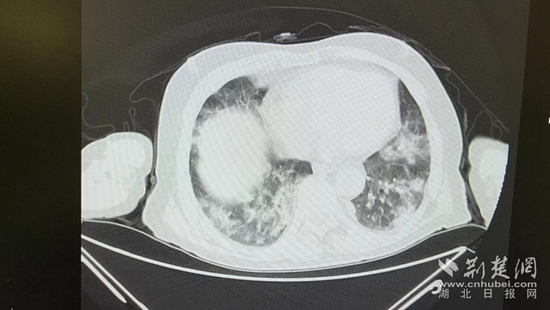

病情的突然惡化,會不會與近期的新冠病毒感染有關(guān)?雖然家屬反映,曾多次在家自測抗原正常,但徐濤還是力排眾議,說服老人進行核酸檢測和肺部CT檢查。結(jié)果顯示核酸陽性,60%白肺,結(jié)合老人的表現(xiàn),這正是一例典型的老年人“沉默性肺炎”。

胸部CT片。通訊員 供圖